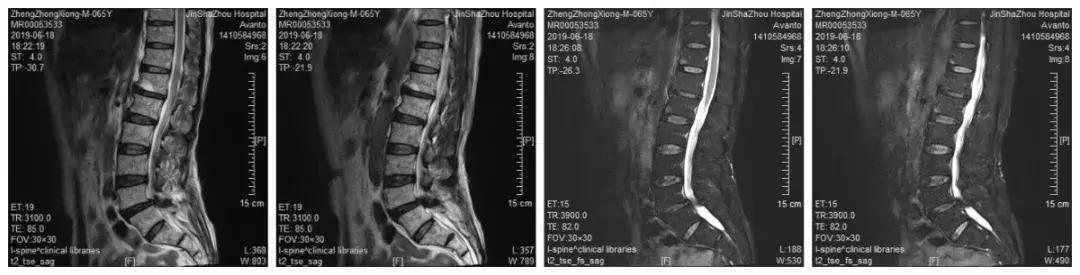

影像学检查